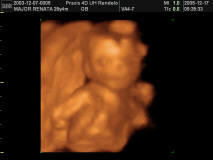

4D

2005.12.17. 15:44

szégyenlős

fogom a fejem:-)

mosoly, 1 kéz, 1 láb